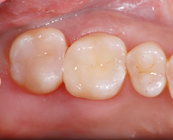

奥歯の詰め物

Before

After

ダイレクトボンディング

白いペースト上の素材を、直接お口の中で盛り付けていく治療です。通常の歯科治療に比べ、歯を削る量を減らせるだけでなく、型取りをする必要もないので1日で治療が完了することも魅力の1つです。